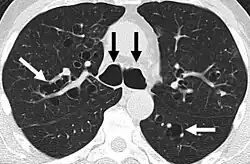

- Bronquiectasias quísticas: dilataciones saculares de los bronquios que aparecen en enfermedades como la fibrosis quística o la discinesia ciliar primaria.